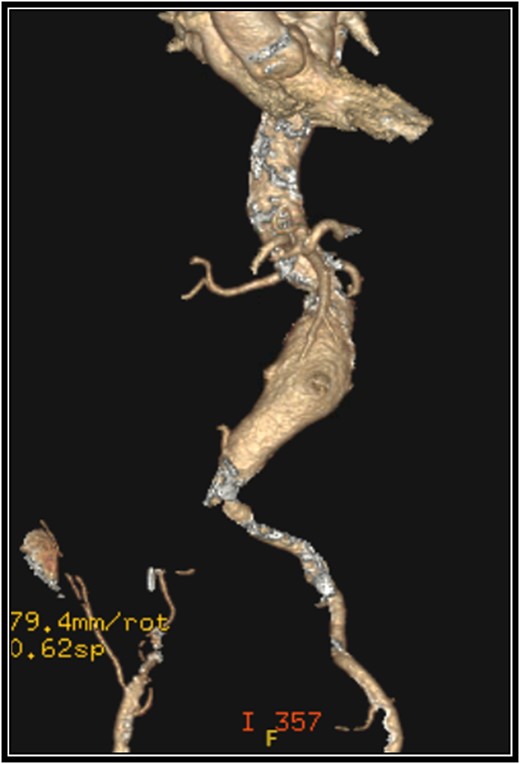

A 79-year-old female with past medical history of peripheral arterial disease, chronic obstructive pulmonary disease on 4 L oxygen baseline, history of tobacco use, and hypertension presented with an enlarging abdominal aortic aneurysm measuring 5.2 cm and chronic occlusion of the right common iliac artery secondary to vascular disease. The abdominal aneurysm was 3.5 cm 6 years ago, but a recent MRI for back pain found it had grown to 5.2 cm. The patient lives a sedentary lifestyle, primarily uses a wheelchair, ambulates a limited amount with a walker, and experiences dyspnea on exertion. She denies claudication symptoms. A CTA was completed for preoperative planning (Fig. 1).

Preoperative 3-D reconstruction based on CTA imaging demonstrating an infrarenal abdominal aortic aneurysm and complete occlusion of the right common iliac artery with distal reconstitution.